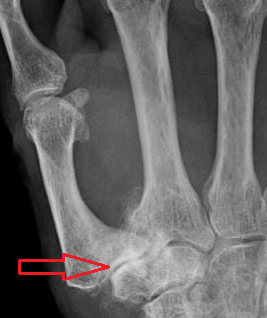

It is believed that laxity of the ligaments surrounding the CMC1 joint is the main cause of CMC OA.[16] Especially laxity of the most significant ligament, the palmar beak ligament, will lead to joint instability.[16] This instability causes misalignment of the joint bones, which will then rub against each other. As a consequence, the cushioning cartilage, which covers the surfaces of the joint bones, wears down.[1] The synovial membranes get irritated and synovitis occurs. Eventually, the bare surfaces of the joint bones are exposed to each other. The gap between the joint bones decreases, as there is hardly any cartilage left.

In reaction of this process the joint bones thicken at the surface, resulting in subchondral sclerosis. Also bony outgrowths, called osteophytes, are formed at the joint margins.[17]

Classification according to Eaton and Littler[22]

CMC OA can be divided into different stages which show the progression of the disease. The most commonly used classification is the radiological staging protocol according to Eaton and Littler. Four different stages are distinguished on radiological evidence of synovitis, joint space and capsular laxity.[20]

Stage 1:

- "synovitis phase"

- slight widening of the joint space

- articular contours are normal

- < 1/3 subluxation of the joint (in any projection)

Stage 2:

- There is a significant capsular laxity

- 1/3 subluxation of the joint

- Osteophytes, < 2 mm in diameter, are present. (usually adjacent to the volar or dorsal facets of the trapezium)

Stage 3:

- > 1/3 subluxation of the joint

- Osteophytes, > 2 mm in diameter, are present (usually adjacent to the volar and dorsal facets of the trapezium)

- Slight joint space narrowing

Stage 4:

- Major subluxation of the joint.

- Very narrow joint space

- Cystic and sclerotic subchondral bone changes are present

- Significant erosion of the scaphotrapezial joint.